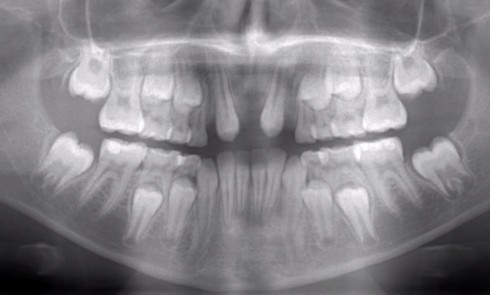

L’âge de survenue de ces traumatismes se situe entre 8 et 12 ans. À cet âge, les incisives permanentes ont...